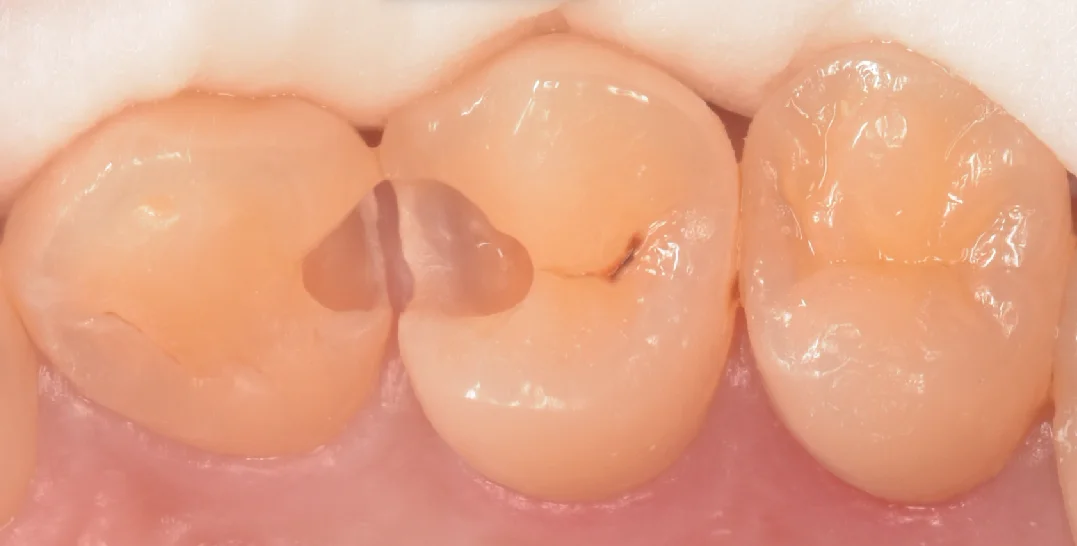

さて、虫歯を取り切ったのがこちらになります。

綺麗な歯の色が出たのがわかると思います。

こう言った歯との間の治療を行う際に私が意識していることの1つに、「歯茎側のエナメル質はなるべく残す」というのがあります。

これは接着修復に携わる歯科医師ならほぼ全員知っていることではありますが、歯の最表層に存在するエナメル質と歯の内部に存在している象牙質は接着力が大きく違います。

エナメル質の方が圧倒的に接着力が強く、また後々の加水分解も起こってこないため、この部分にエナメル質が残存しているかどうかは長期予後を得られるかどうかに大きな影響があると私は考えているからです。

そして治療完了後の写真がこちらになります。

違和感なく綺麗に詰め終われたかと思います。

歯の溝の形態がやや特徴的で、私が良くやるデザインだと違和感が出そうだったため、後ろ半分の部分のデザインを模倣する形で詰めていきました。

歯の形自体もやや難しかったですが、問題なく歯とのあたりも再現できたと思います。

フロスも引っかからず段差もない状態ですので、しっかりと管理していけば長期的に安定して使っていけると思います。